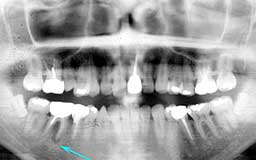

★ Uさん 38歳

当時の時代背景ということもあって、初診時38歳だったUさんのケースは少し特殊です。

メインテナンスは程度に応じて3か月・6か月・1年毎を選択するのが望ましいという保険上の

指導があったことも影響しています。多少将来が危ぶまれるものの、今すぐに何かが起こる

可能性は少ないという判断をしたUさんには3か月毎のメインテナンスを指示しました。

| Uさん 初診時 38歳 男性 歯槽骨破壊はそれほど著明ではないが、同じ年代のひとと比べれば歯槽膿漏の進行が少し 強そうな感じでした |

Uさん 20年後 57歳 長年にわたり変化のない推移だったがここ数年で急激な骨破壊を観察 |

話は戻りますが、そんななかでUさんは、唯一20年間3か月毎のメインテナンスを継続され

た貴重な存在でした。危ないから毎月に変更してもらおうと思いつつ、確実に3か月毎の予約

を守るUさんの診療態度とそれでも大きな変化もなく十分現状維持が保てている実績があって

そのままになっていました。ここ最近、左右の下顎臼歯部に急激な骨欠損が確認されたことか

ら、1か月毎のメインテナンスに切り替えることにしました。